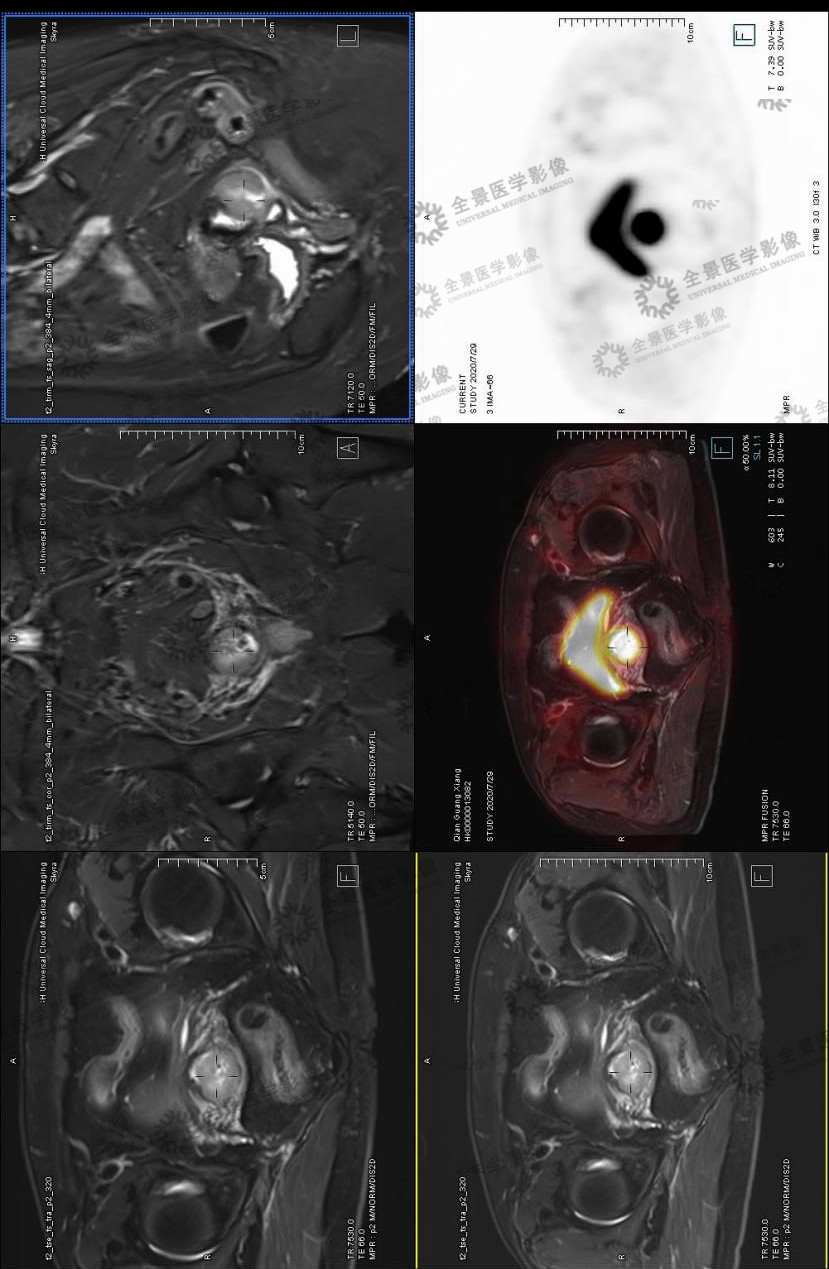

病史:女 52阴道分泌物多半年。2020-7-13B超:颈管内实质占位 血供丰富,2020-7-22宫颈活检:低分化腺癌 腺鳞癌待除外,HPV结果未出,为排除远处转移来诊。无慢性病史,无药敏史。

宫颈异常强化灶伴FDG摄取增高,考虑为宫颈癌,累及子宫峡部及阴道上段(右侧壁为主)。